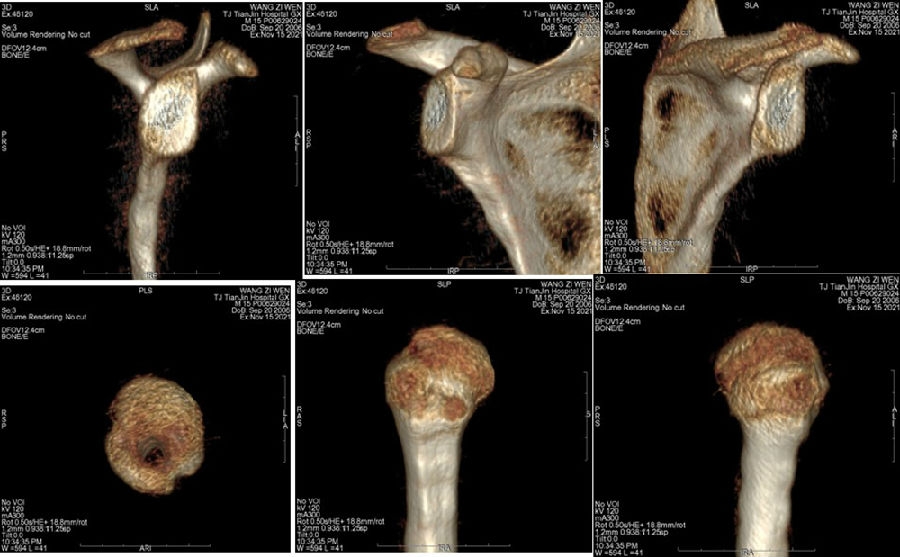

典型病例,王XX,男性,15岁。主诉右肩外伤疼痛、活动受限1月。既往半年前有肩关节脱位病史。

图37 既往肩关节脱位时,急诊所拍的X线片

图38 复位后的肩关节CT

双侧CT三维扫描显示:D=34mm,d=3mm,d/D=肩胛盂骨缺损9%;GT=25.2mm,HIS=30mm。

该患者为轨迹外Hill-Sachs损伤,需要做bankart修补,同时轨迹外做remplissage手术。

肱骨头后上可见Hi11-sach损伤,HIS=3cm,软骨磨损消失,裸露硬化骨质。 于Hi11-sach损伤部位植入4.5mm corkscrew 1枚(备最后收紧)——Remplissage。